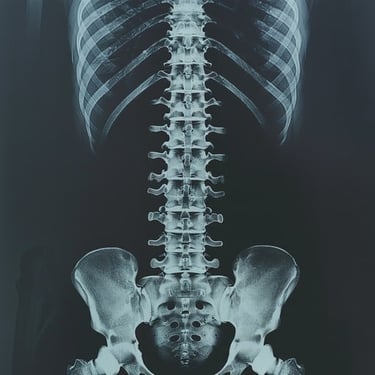

Sivam Hospital – Advanced Spine Surgery in Chennai

At Sivam Hospital, we specialize in spine surgery and spinal care, offering expert solutions for back pain, slipped discs, spinal deformities, and nerve compression. Our spine specialists use advanced surgical and minimally invasive techniques to relieve pain, restore function, and improve mobility.

We provide comprehensive care from diagnosis to rehabilitation, making Sivam Hospital a trusted center for spine surgery. With modern operation theatres, advanced imaging, and dedicated physiotherapy support, we ensure safe procedures, quicker recovery, and long-lasting results.

👉 Why Choose Sivam Hospital Spine Surgery?

Expertise in Slipped Disc, Spinal Fusion & Deformity Correction

Minimally Invasive & Endoscopic Spine Surgery Options

Advanced Operation Theatres & Imaging Facilities

Personalized Pain Management & Rehabilitation Programs

Safe, Reliable & Patient-centered Spine Care

Stand tall, move freely. Trust Sivam Hospital for advanced spine surgery and comprehensive spinal care.